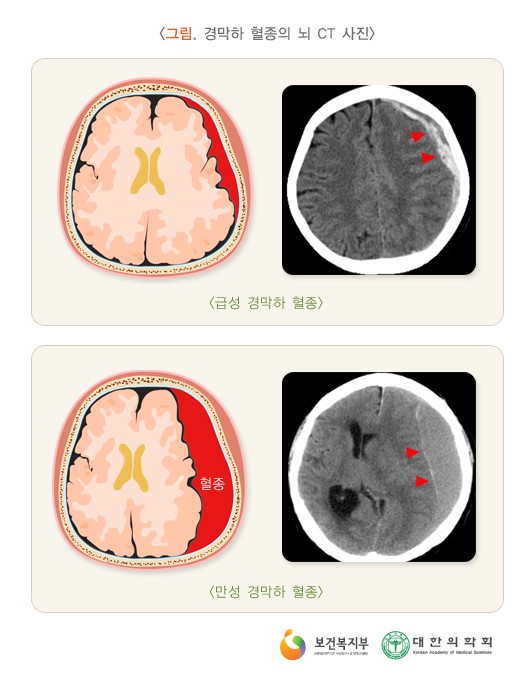

4. 진단

2) 영상 검사 : 뇌와 척수에 출혈이 있는지 확인합니다.